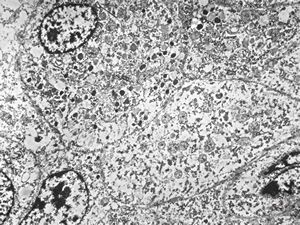

F, 72y. | carcinoid … metastasis to lymphonode